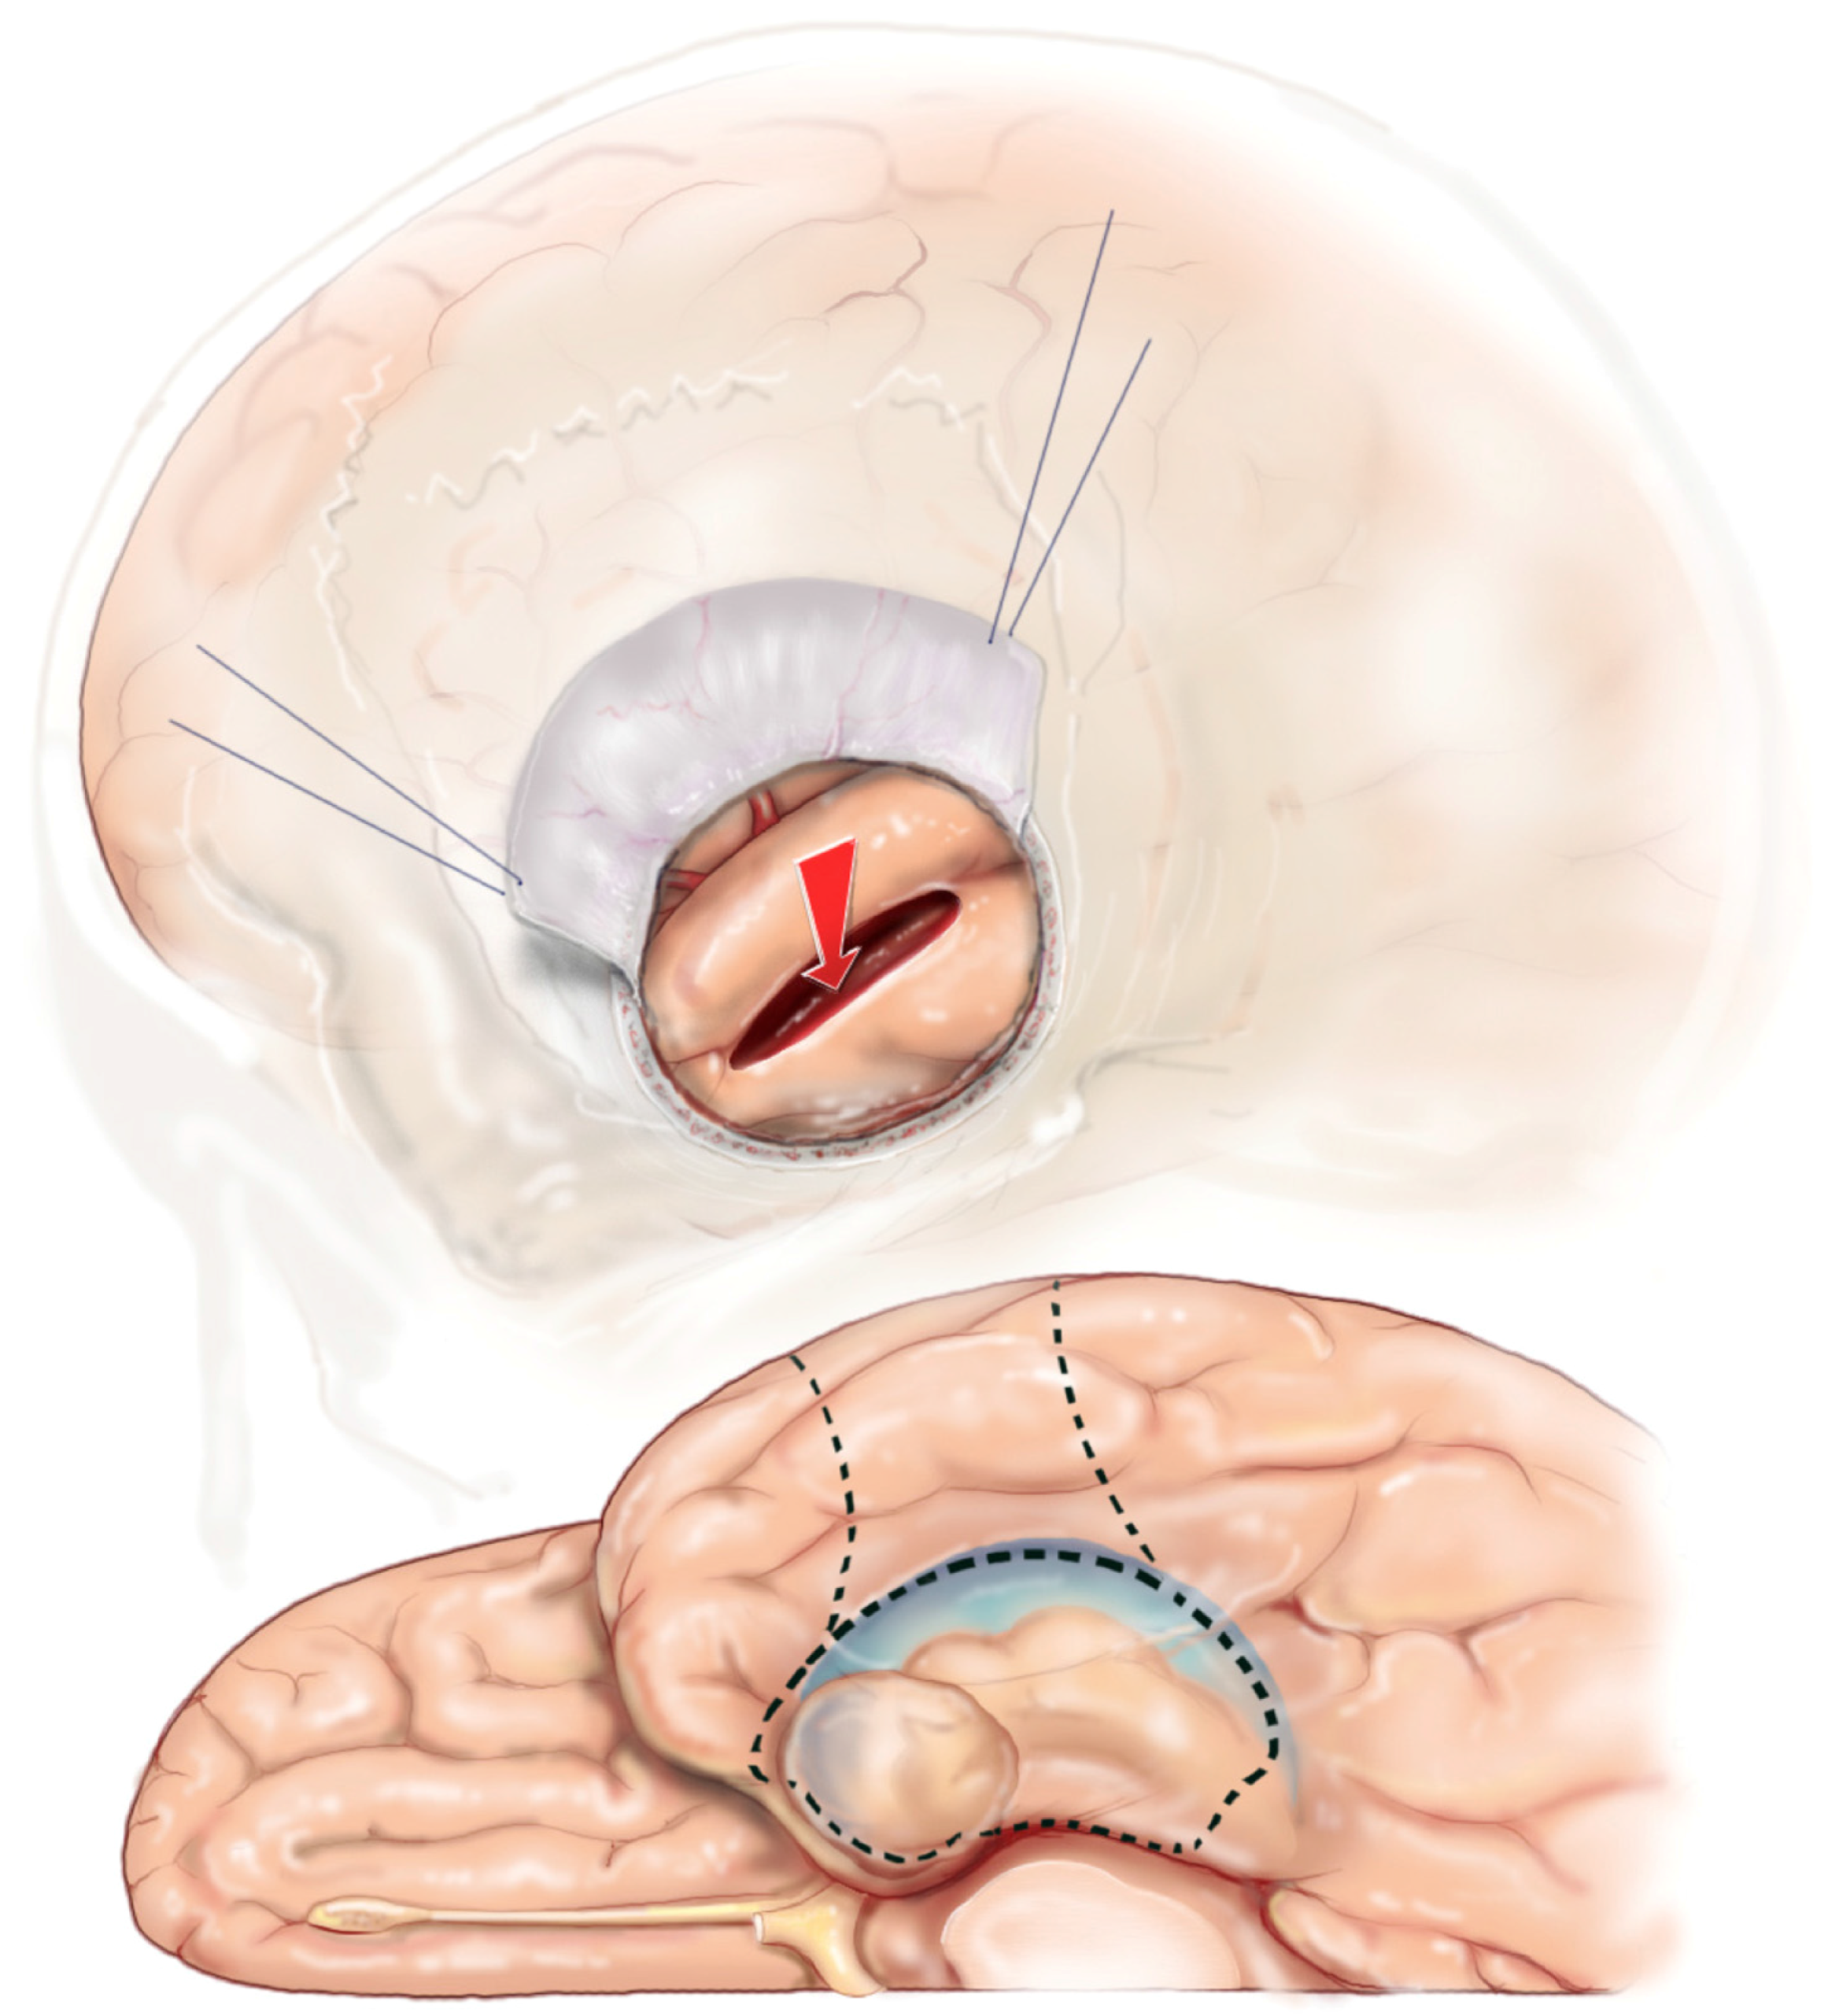

A corticectomy along the superior aspect of the second temporal gyrus (T2) is made to begin the corridor to the mesial temporal structures. A 2 to 3 cm corticectomy provides sufficient working space. Figure 5 The posterior extent of the corticectomy is limited by the central sulcus in the non-dominant hemisphere and by the precentral sulcus in the dominant hemisphere. Image guidance is sufficient to localize precentral and central sulcus, which corresponds to about 3.5 cm and 4.5 cm from the temporal tip, respectively. The author has found that using an ultrasonic aspirator at the lowest settings of aspiration and amplitude to be the best subpial dissection and aspiration tool. A corridor is fashioned down to the temporal horn that is opened, which is typically 3–4 cm deep from the cortical surface. The corridor trajectory parallels the superior temporal sulcus, which points to the temporal horn and stops just short of it. A retractor is inserted once the temporal horn is opened to facilitate fully exposing the mesial temporal structures by opening the ventricle from its anterior most tip to the posterior limit of the corridor Figure 6.

Figure 5. SAH corticectomy of about 2.5 cm is made along T2 just below the superior temporal sulcus. A white matter corridor is fashioned that follows the superior temporal sulcus down to the temporal horn, which is opened to visualize directly the mesial temporal structures.

Figure 6. Reprinted from Journal of Clinical Neuroscience 17 (9), Boling W, Minimal access keyhole surgery for mesial temporal lobe epilepsy, 1180–1184, Copyright 2010, with permission from Elsevier, [59]. Coronal view of the temporal lobe and nearby structures. A retractor is placed along the white matter corridor after opening the ventricle to fully expose its contents. The first step in the SAH is to enter the lateral ventricular sulcus (star) that lies between the bulges into the ventricle of the hippocampus and collateral eminence in order to empty the parahippocampus in a subpial fashion. Dotted line illustrates mesial temporal structures to be removed in this view, namely the hippocampal complex and parahippocampus. SF = Sylvian Fissure, T1= superior temporal gyrus, T2 = middle temporal gyrus, T4 = Fusiform gyrus, T5(PH) = parahippocampal gyrus.